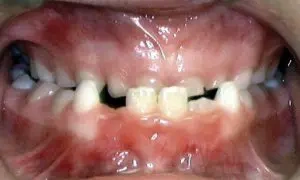

Openbite

Proper chewing is impacted by this type of bite, in which the upper and lower front teeth do not overlap. Openbite may cause a number of unwanted habits, such as tongue thrusting.